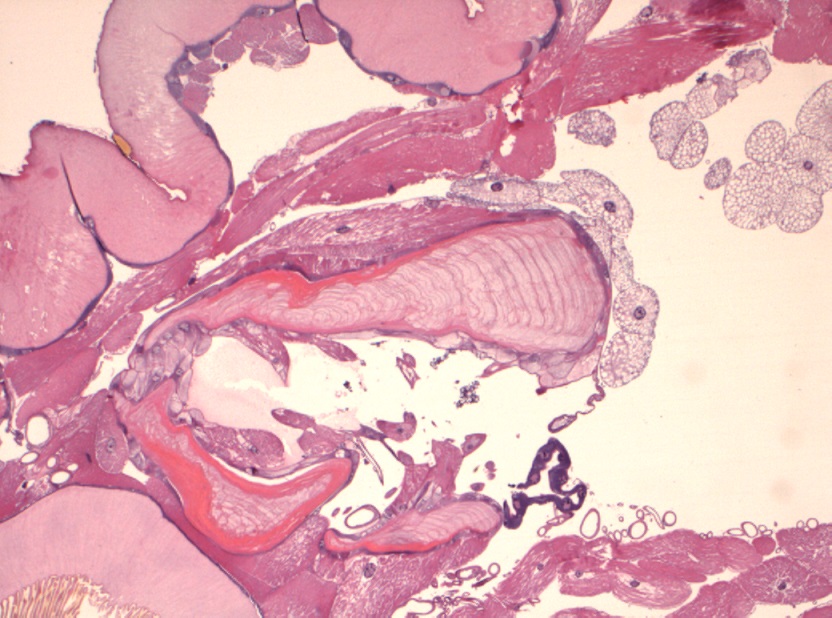

Foto microscopiche: purtroppo non ho potuto fare foto "panoramica"; ho fatto alcune foto al minore ingrandimento; si possono osservare le componenti della larva caratterizzata da spessa cuticola con sparse "spine" in superficie, che penso che siano i rostri; internamente alla cuticola si osserva strato di tessuto muscolare liscio ed organi interni conservati; ho fatto anche una foto del lembo di cute e sottocute sovrastante centrato da tragitto fistoloso circondato da denso infiltrato infiammatorio costituito da linfociti, plasmacellule, istiociti e più rari granulociti eosinofili.

Io vi metto due foto macroscopiche e quelle istologiche, che in pratica rappresentano le "fette" della larva partendo da un'estremità (bocca?), poi il centro (forse l'apparato digerente?) e l'altra estremità...spero siano sufficienti :)